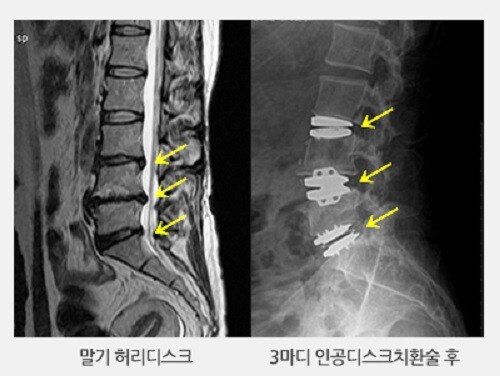

허리디스크에 대해 아직 살펴보지 못하셨다면 허리디스크가 어느 부위를 말하는지 확인하시고 시기에 맞추어 운동하여 주십시요.